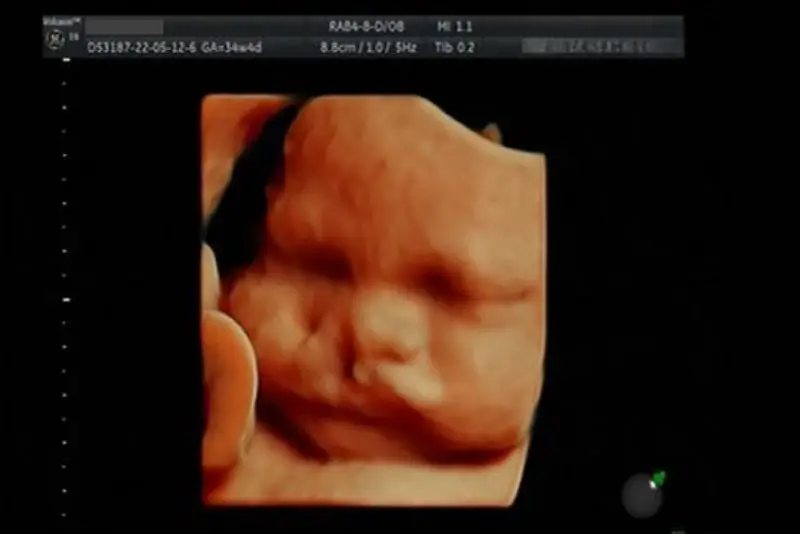

- Tuần 20–24: Công nghệ siêu âm 3D và 4D cho phép quan sát chi tiết các cấu trúc khuôn mặt và phát hiện dị tật. Hình ảnh trực quan giúp bác sĩ và cha mẹ dễ hiểu về tình trạng của thai nhi. Phát hiện sớm giúp chuẩn bị các bước can thiệp phù hợp sau sinh.

Siêu âm thai phát hiện hở hàm ếch

- Siêu âm 3D, 4D: Các công nghệ tiên tiến này tạo ra hình ảnh sắc nét hơn, hỗ trợ bác sĩ quan sát rõ các dị tật. Phương pháp này giúp đánh giá chi tiết hình dạng môi, vòm miệng và các bất thường khác. Việc quan sát trực quan giúp cha mẹ nắm rõ tình trạng thai nhi.

Có trường hợp hở hàm ếch khó phát hiện nếu dị tật chỉ xuất hiện ở vòm miệng mà không kèm theo hở môi, vì phần vòm miệng nằm sâu và khó quan sát hơn trong siêu âm. Trong những trường hợp này, chẩn đoán có thể cần thêm các phương pháp hình ảnh học khác hoặc siêu âm 3D/4D.

Siêu âm giúp phát hiện hở hàm ếch ở thai nhi